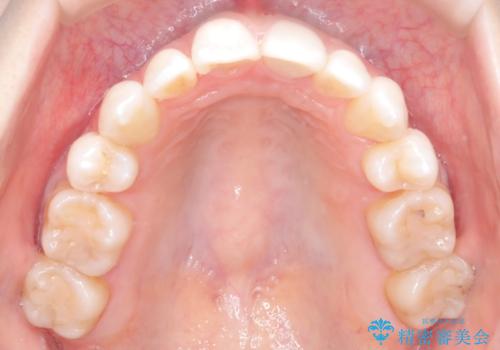

ハーフリンガル矯正|上下4本の抜歯で叢生を改善し、美しい歯並びへ

- 患者様は、歯並びの乱れ(叢生)を整えたいが、前歯の突出感は気にならないとのことで来院されました。診察の結果、全体的な歯列のスペース不足により抜歯が必要と判断。しかし、前歯を大きく下げる必要はなかったため、小臼歯の中でも5番(第二小臼歯)を抜歯する治療計画を立てました。装置は、上顎が舌側(リンガル)、下顎が表側(審美ワイヤー)のハーフリンガル矯正を採用し、目立ちにくさと効率的な歯の移動を両立しました。

抜歯によって歯を並べるためのスペースを確保。その後、ハーフリンガル矯正を用いて、上顎は舌側から、下顎は目立ちにくいワイヤーで歯を誘導し、歯列全体を整えました。治療期間を通じて、噛み合わせのバランスも改善し、機能的にも審美的にも理想的な仕上がりとなりました。患者様からは「目立たずに矯正でき、きれいな歯並びになって嬉しい」とご満足いただきました。